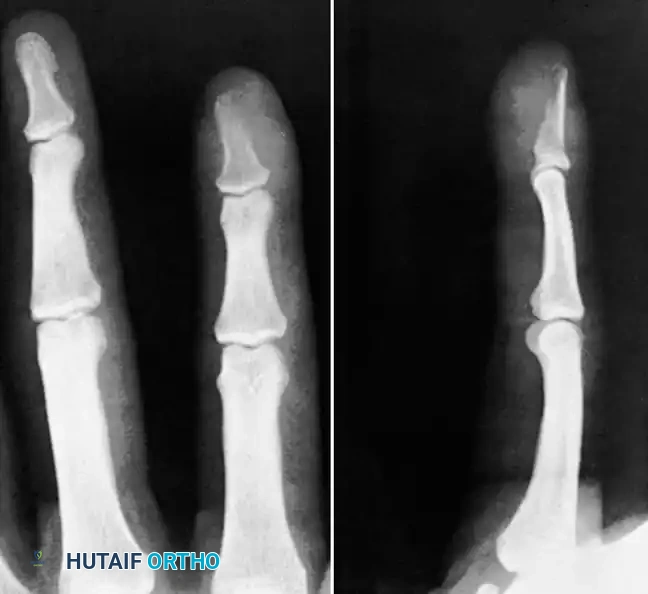

Fig. 75-14 Osteitis of distal phalanx caused by infection in finger pulp.

Fig. 75-15 Sequestrating osteomyelitis of middle phalanx.